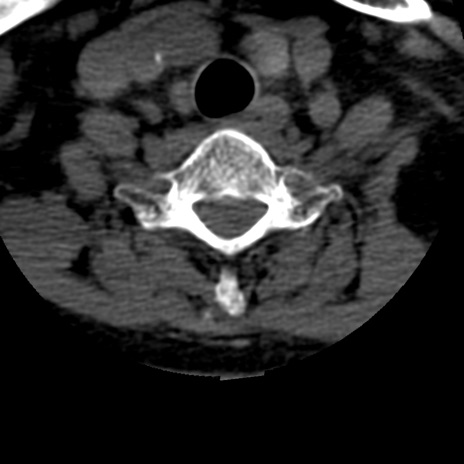

症例50 頚椎CT(横断像)

頚椎CT